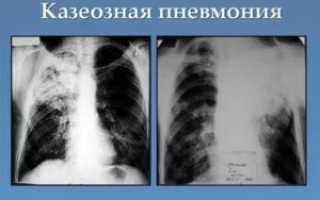

Тотальное затемнение легкого на рентгеновском снимке представляет собой полное или частичное затемнение (не менее 2/3 легочного поля). При этом возможны просветы в верхней или нижней части легкого.

Основными физиологическими причинами проявления такого синдрома являются отсутствие воздуха в полости легкого, увеличение плотности ткани всей поверхности легкого, содержание в плевральной полости жидкости или какого-либо патологического содержимого.

К болезням, способным вызвать подобный синдром можно отнести:

- ателектаз;

- цирроз;

- экссудативный плеврит;

- пневмония.